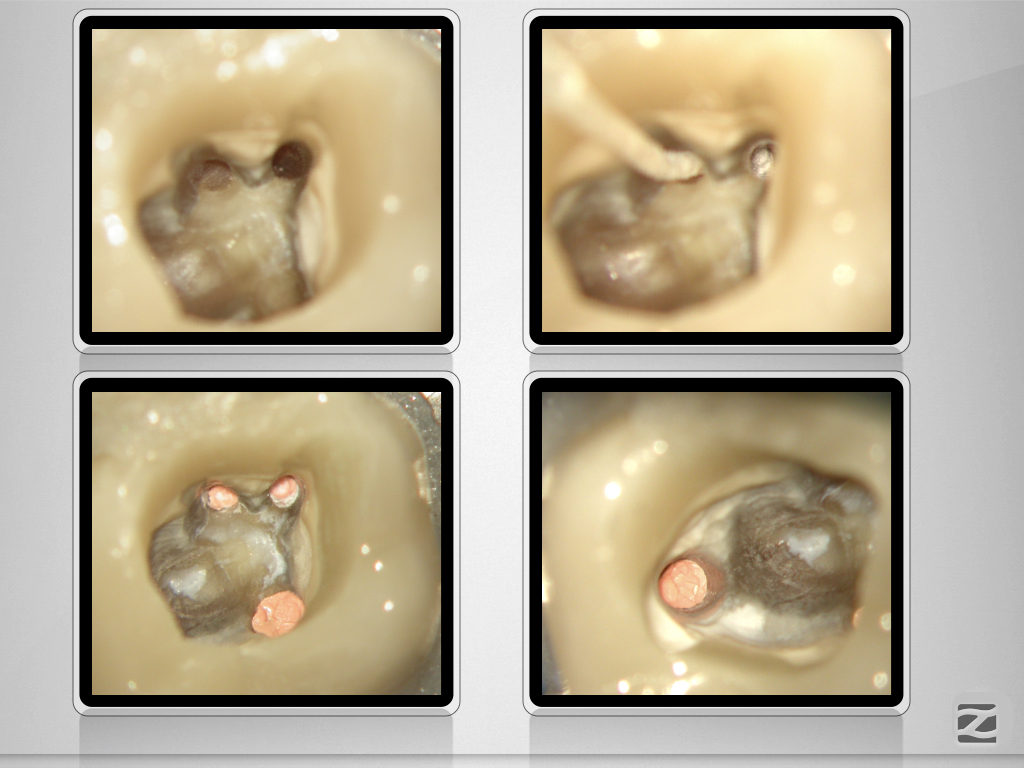

Wie hältst Du es mit dem Haarriss?